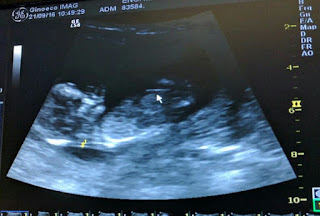

Ecografia das 12 semanas

E está tudo bem com o nosso bebé!

Continuamos com um pequeno descolamento mas que não está a afectar o crescimento do bebé, o médico disse que até seria normal ter atrasado um bocadinho o crescimento, mas não, está impecável para o tempo que tem!

Um bocadinho de alívio depois do susto, mas é para continuar o repouso em casa. Enquanto houver descolamento não há dúvida de que tenho de ficar de baixa.

Tudo para que o bebé cresça bem!